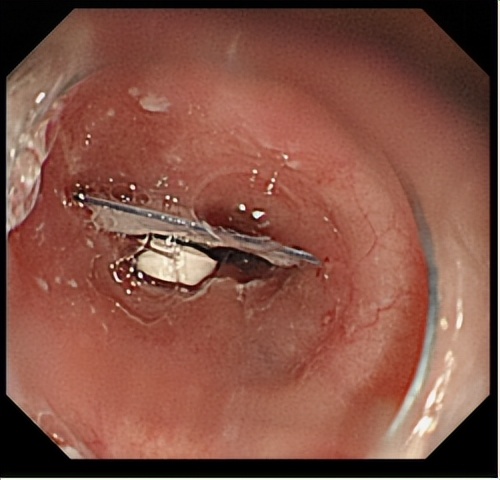

当天下午5时左右,在麻醉医师的保驾护航下,由付肖岩主任医师指导陈小玲主治医师操作,在依姆食管距门齿约30cm处发现异物(药品铝制外包装),用异物钳将异物取出,大小约2cmx2cm。“取出异物后可见食管黏膜已轻度损伤,有少许出血,用生理盐水冲洗后未再明显渗血。”陈小玲医师介绍。

胃镜下看到,药片和铝制包装卡在食道